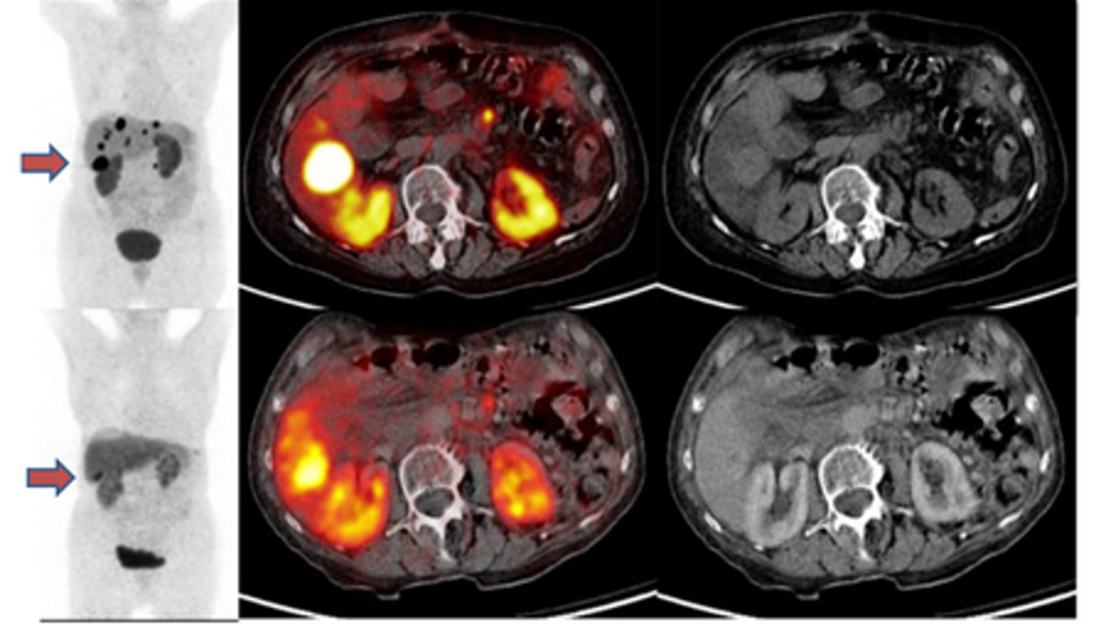

Status vor PRRT (obere Reihe)

Status nach PRRT (untere Reihe)

Abb. entnommen aus: Ezziddin S, et al. Outcome of peptide receptor radionuclide therapy with 177Lu-octreotate in advanced grade 1/2 pancreatic neuroendocrine tumours.Eur J Nucl Med Mol Imaging.2014;41(5):925-33.

45-jährige Patientin mit pankreatischem NET (Grad 3) und Lebermetastasen zeigte Progression nach Chemotherapie (Etoposid/cis-Platin). Ein dramatischer Rückgang der Tumorlast konnte nach sechs Behandlungszyklen mit Lutetium-177 Peptidrezeptor Radiotherapie (PRRT) mittels 177Lu DOTATATE festgestellt werden. Das Therapiemonitoring erfolgte mittels 68Ga DOTATOC PET Bildgebung.

34-jähriger Patient mit pankreatischem NET (Grad 3) und Lebermetastasen zeigte Progression nach Chemotherapie (5-FUSTZ). Partielle Remission konnte nach vier Behandlungszyklen mit Lutetium-177 Peptidrezeptor Radiotherapie (PRRT) mittels 177Lu DOTATATE erreicht werden. Das Therapiemonitoring erfolgte mittels 18F-FDG PET Bildgebung.